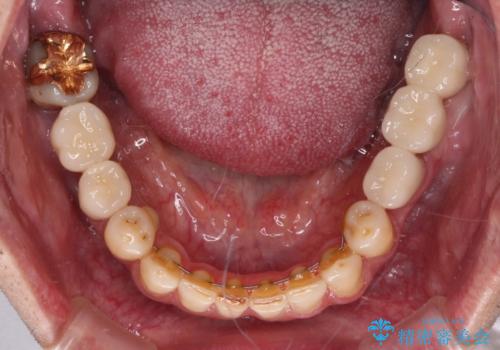

下顎の部分矯正を行ってから奥歯の補綴治療とインプラント治療

並行して左下にはインプラントを埋入し、上顎臼歯部の気になる部分も根管治療などを進めて行き、矯正治療を終えると同時に補綴治療を行うこととしました。

奥歯1歯分を動かすには時間がかかるため、矯正治療には思いの外時間がかかりました。

痛みのある奥歯は必要に応じて根管治療を行い、左下インプラントは角化歯肉の移植により清掃性を向上させ、気になっていた部分をしっかりと改善させることができました。